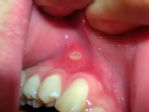

Uzman Diş Hekimi ve Protez Uzmanı Dt. Sevgen Eralp, “Aft, en sık rastlanan ağız yaralarından biridir. Aft dilde, yumuşak damakta, dudak ve yanakların iç kısımlarında görülen küçük, yüzeysel ülserlerdir. Oldukça ağrılıdırlar ve ne yaparsanız yapın 5-10 gün geçmeden iyileşmezler. Neyse ki bakteriyel ya da virüs kaynaklı olmadığı için kişiden kişiye bulaşması gibi bir durum söz konusu değildir” dedi.

Aft görülen durumlarda herhangi bir tedavi yapılmasa bile en geç 10 gün içinde iyileşme olacaktır. Aftın daha hızlı iyileşmesini sağlayacak medikal bir tedavi maalesef yoktur. Fakat bu dönemi daha az ağrılı atlatmak mümkündür. Aft görülen dönemde, acı ve baharatlı yemeklerden uzak durmak, aşırı sıcak yiyecek ve içeceklerden uzak durmak tavsiye edilebilir. Çok rahatsız eden durumlarda doktorunuzun size önereceği, eczanelerde satılan ürünlerden kullanabilirsiniz. Bu ürünler aftın üzerine sürüldüğünde, aftı ağız içi ortamdan izole edecek ve mekanik olarak zarar görmesini engelleyecektir. Yine doktorunuzun önerebileceği nikotinli gargara solüsyonları da kullanılabilir. Ama en doğrusu doktorunuza muayene olmanız ve reçetenize uygun bir ilaç kullanmanız olacaktır” diye konuştu.